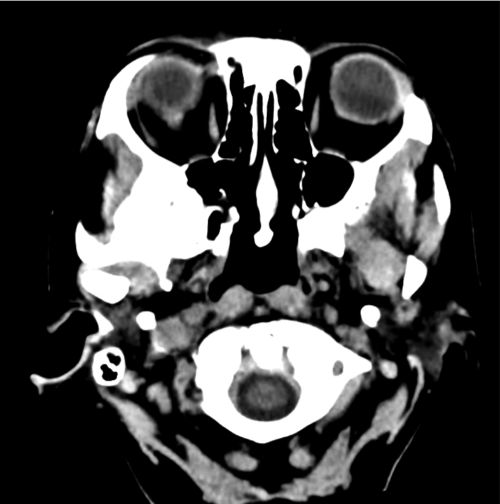

CT scan showing mass

This image encapsulates a critical moment in diagnostic imaging. The delineation of the mass, depicted with striking clarity, offers essential insights into the nature of the anomaly. Such scans become instrumental in forming hypotheses about the underlying conditions—each pixel perhaps holding the key to unraveling complex medical narratives.

ct-mass_01 – Differential Diagnosis of

A close examination of this CT depiction invites viewers to ponder the myriad possibilities embedded in the image. It serves as a cornerstone in the history of differential diagnosis, where careful scrutiny and keen analytical abilities reign supreme. Here, the radiologist’s eye becomes an investigator, sifting through layers of information to distinguish benign from malignant findings.